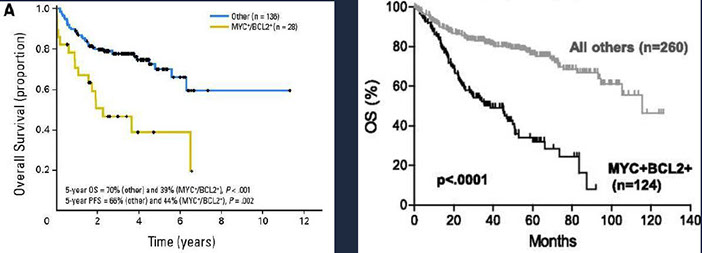

High-grade B-cell lymphoma

- High-grade B-cell lymphoma with MYC and BCL2 and/or BCL6 rearrangements

- High-grade B-cell lymphoma, NOS